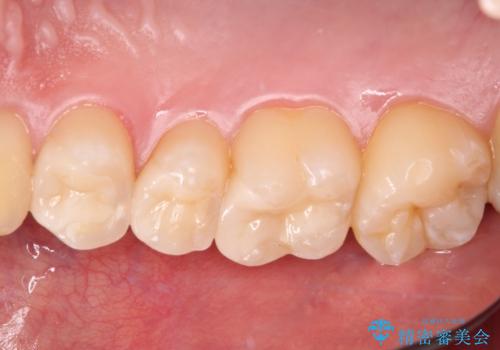

詰め物が外れた セラミックインレー修復

- 以前治療した詰め物が外れてしまい、冷たいものがしみることを主訴として来院された患者様です。

むし歯がないことを確認し、セラミックインレーにて修復するととしました。

適合の良いセラミックインレーの装着により、冷たいものがしみる症状はなくなりました。